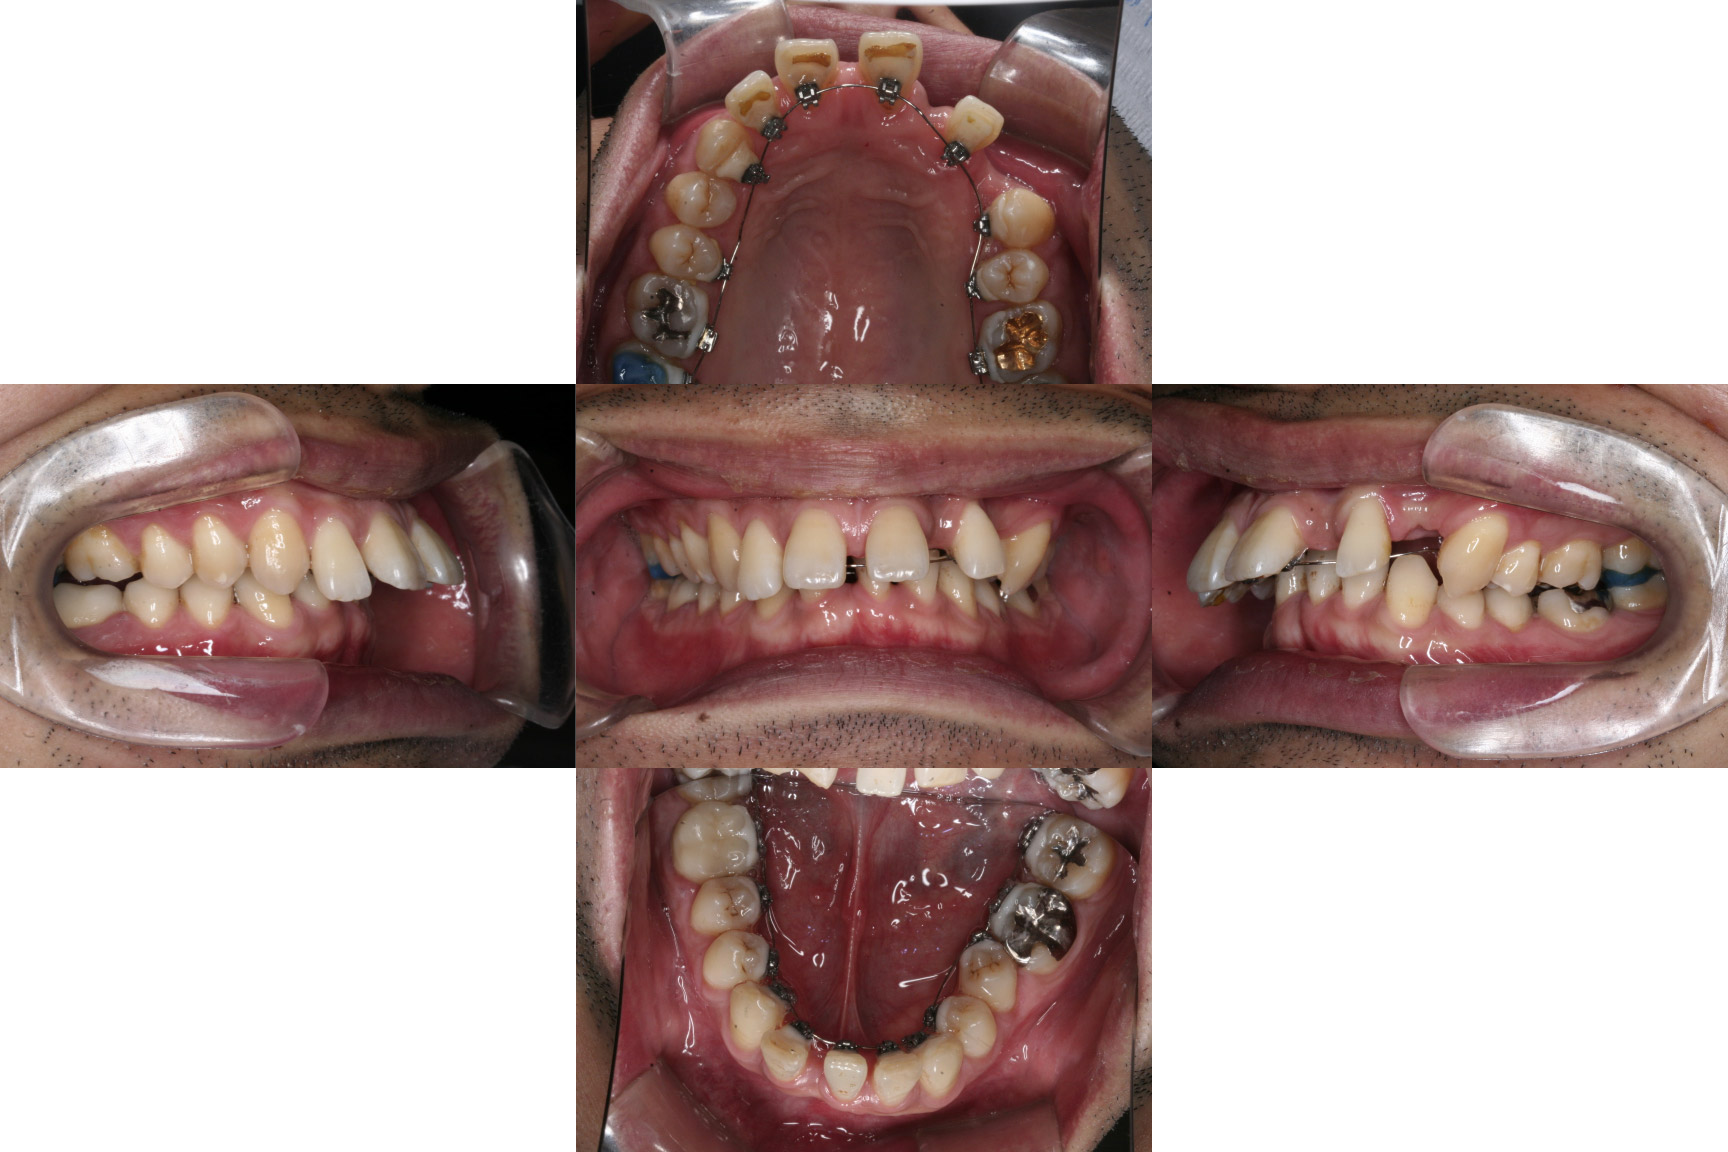

| 主訴 | 【主訴】ディープバイト,すきっ歯 【診断・症状】左上C残存、下顎右下1番欠損、上顎前突、空隙歯列、過蓋咬合 |

| 治療期間 | 約3年半(45回) |

| 抜歯 | 有(左上c、上の4,4) |

| 矯正の装置 | 裏側矯正(舌側矯正) |